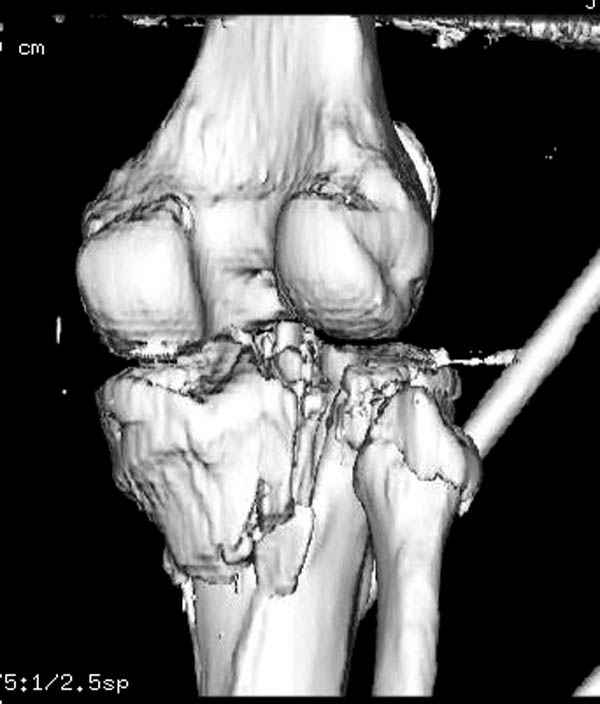

На представленных предоперационных срезах КТ огромный задне-медиальный фрагмент расположен больше кзади, чем медиально. Для планирования, кроме поперечных срезов, надо ориентироваться на корональные срезы, которые укажут топографию верхушки медиального фрагмента.

При сложных переломах тибиал плато для своего рода Damage Control мы иногда применяем поэтапную тактику. Сперва оперируется одна сторона, а потом после рекондиции мягких тканей окончательный этап.

Если состояние мягких тканей позволяет, я бы предложил такой метод для вашего больного. Без предварительного планирования будет трудно, но шанс не надо упускать. Всего несколько дней после операции, и такая тактика лучше, чем недовольный молодой пациент.